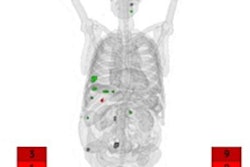

NETs are rare tumors that originate in the neuroendocrine cells of numerous organs, and they are most commonly found in the lungs, gastrointestinal tract, and pancreas. Because the symptoms of NETs can mimic those of other conditions, patients with NETs are often misdiagnosed. By the time NETs are correctly diagnosed, the cancer has often metastasized to other parts of the body.